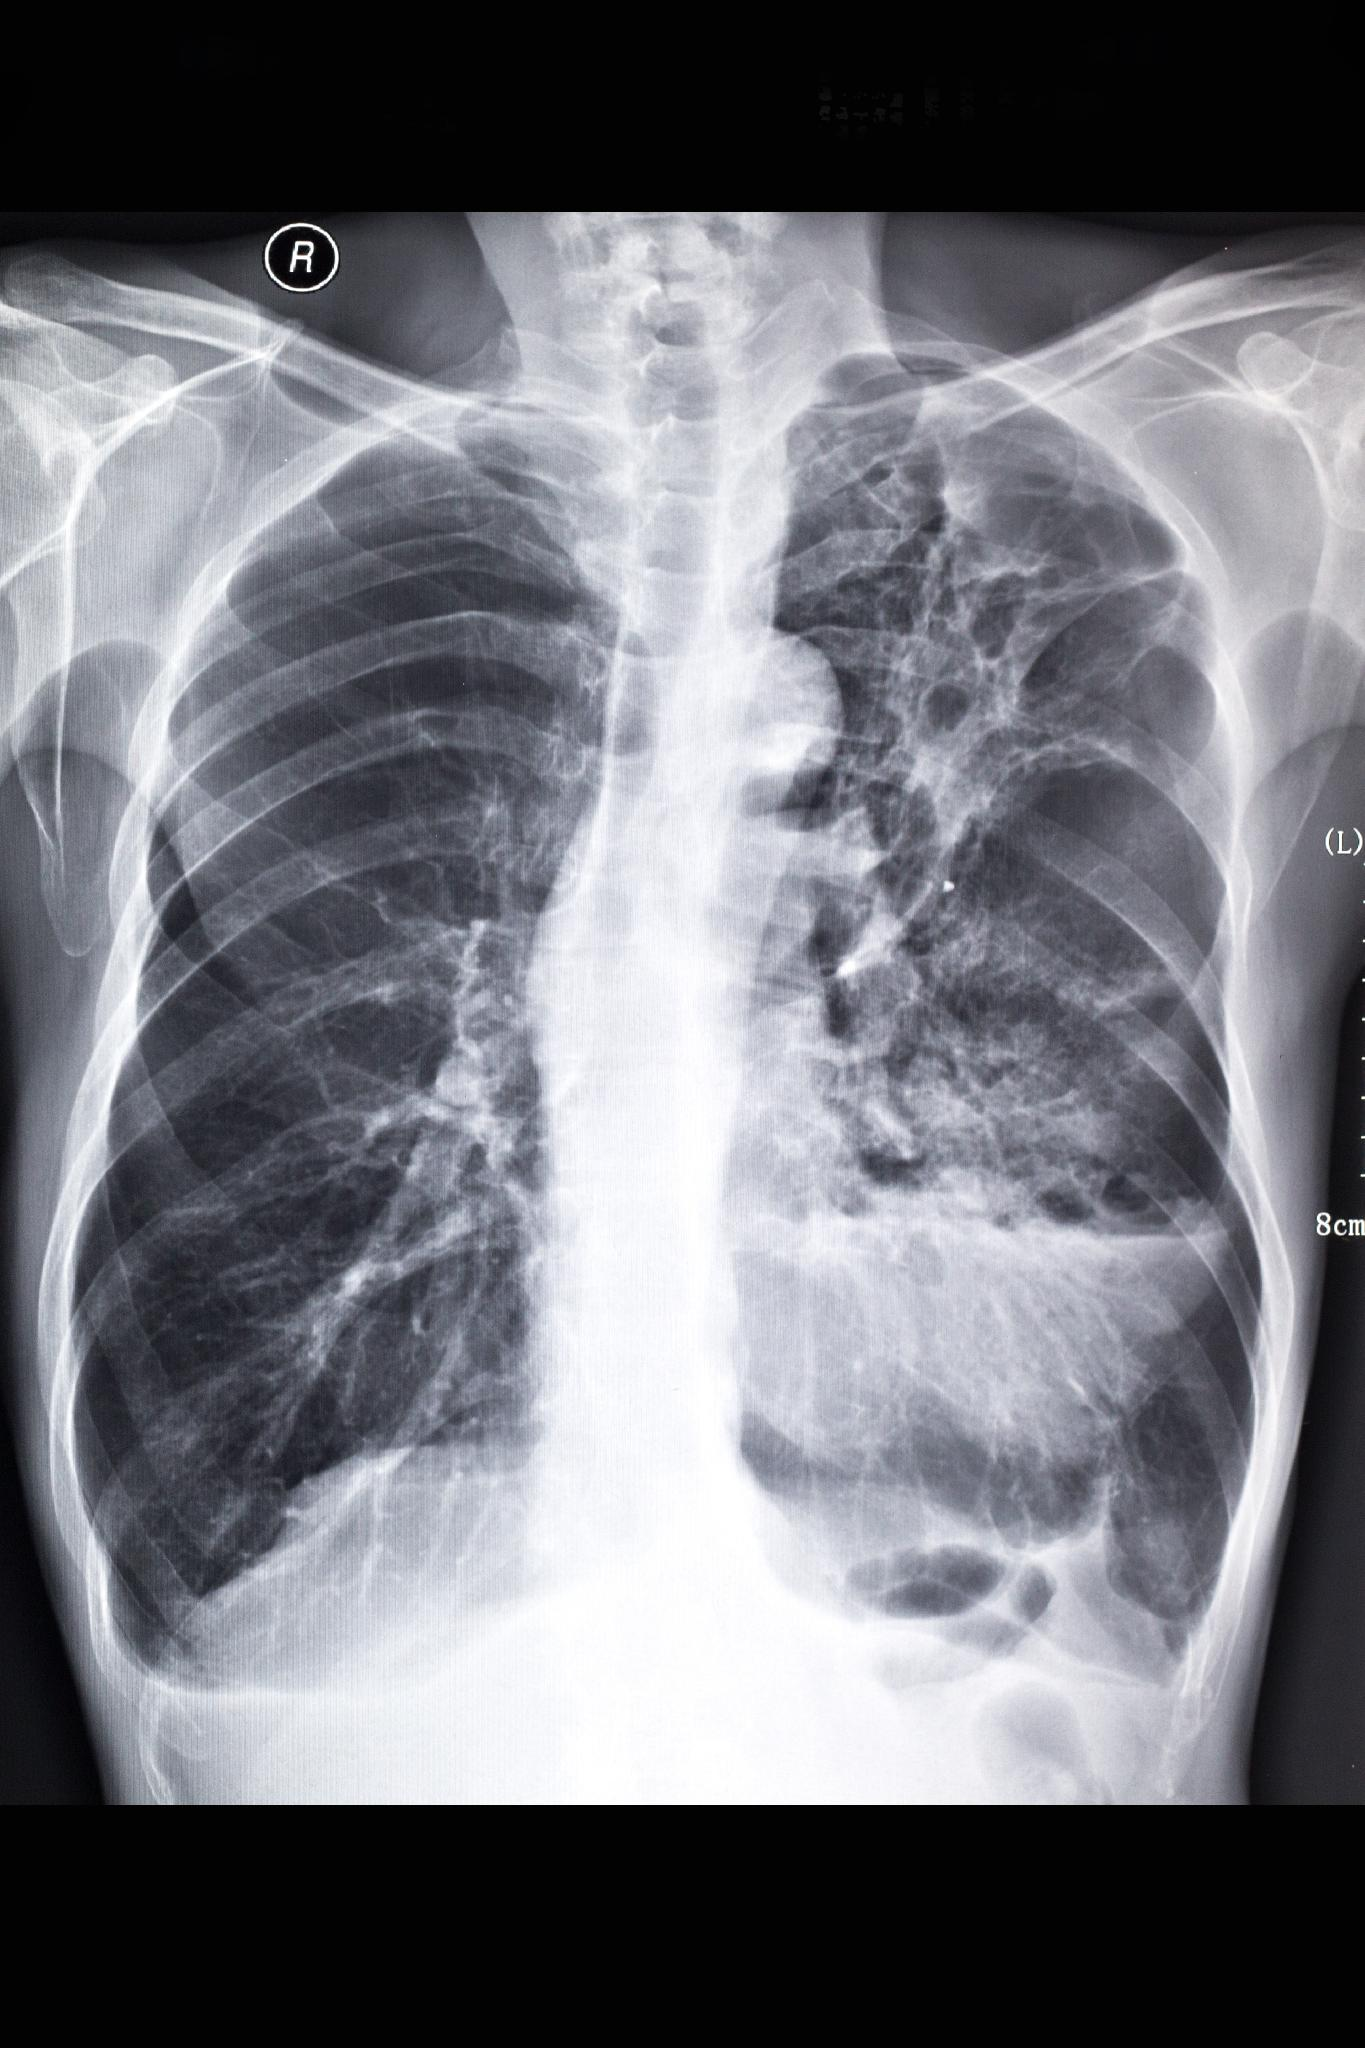

1. X线检查:期常规胸部X线平片不能显示异常,随着病情的进展,95%的患者出现症状时均有胸片的异常,X线表现为云雾状、隐约可见微小点状的弥漫性阴影,犹如磨玻璃(如下图);进一步进展则纤维化表现愈加明显,从纤细的网织状到粗大的网织状,或成网织结节状,以双下肺和外周(胸膜下)明显;晚期更有大小不等的囊状改变,即蜂窝肺,肺容积缩小,膈肌上抬,叶间裂移位。

特发性肺纤维化